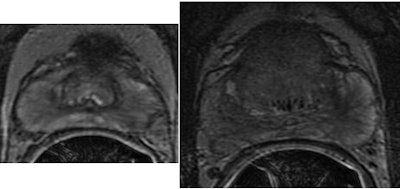

| Original T2-weighted prostate MR images for peripheral zone prostate tumor (left) and central gland prostate tumor (right). All images courtesy of Dr. Satish Viswanath. |